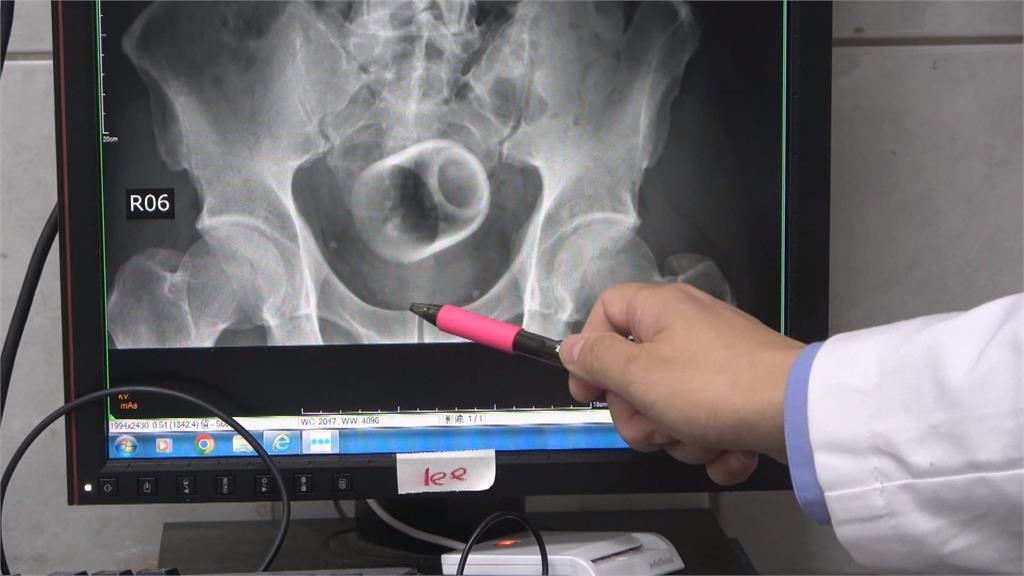

中部中心/陳仕承、陳建華報導台中市一名男子,超過三天無法解便肚痛難耐,到醫院求診,沒想到,X光檢查後竟發現,男子骨盆腔內,有一個喝茶用的陶瓷杯,讓醫師十分驚訝!由於杯子光滑難以用器械取出,最後只好開刀,同時做了一個人工造口,讓患者能夠暫時解便。

台中市一名男子,超過三天無法解便肚痛難耐,到醫院求診,沒想到,X光檢查後竟發現,男子骨盆腔內,有一個喝茶用的陶瓷杯,讓醫師十分驚訝!由於杯子光滑難以用器械取出,最後只好開刀,同時做了一個人工造口,讓患者能夠暫時解便。

綠茶甘醇入喉,但拿來品茶的瓷杯,怎麼莫名其妙,出現在男子的骨盆腔內。X光攝影一照,杯子清晰可見,連看診的醫師,都感到十分詫異。

原來,台中市這名男子,腹脹超過三天無法解便,肚子痛到受不了,不得已到醫院求診,但他起先害羞不提及自己肛門塞了一個杯子,最後在X光檢查之下才被發現,不過由於杯緣光滑,無法使用器械取出,加上杯子全被大腸包住,部分腸子缺血造成壞死,最後只好全身麻醉,開腸破肚取出杯子。醫師表示,肛門塞進異物,臨床上是基於好奇或想要尋求刺激,提醒此舉可能造成肛門括約肌鬆弛失禁,甚至讓腸子壞死破裂,嚴重的話,會引發腹腔感染,併發腹膜炎,甚至有致死危機。